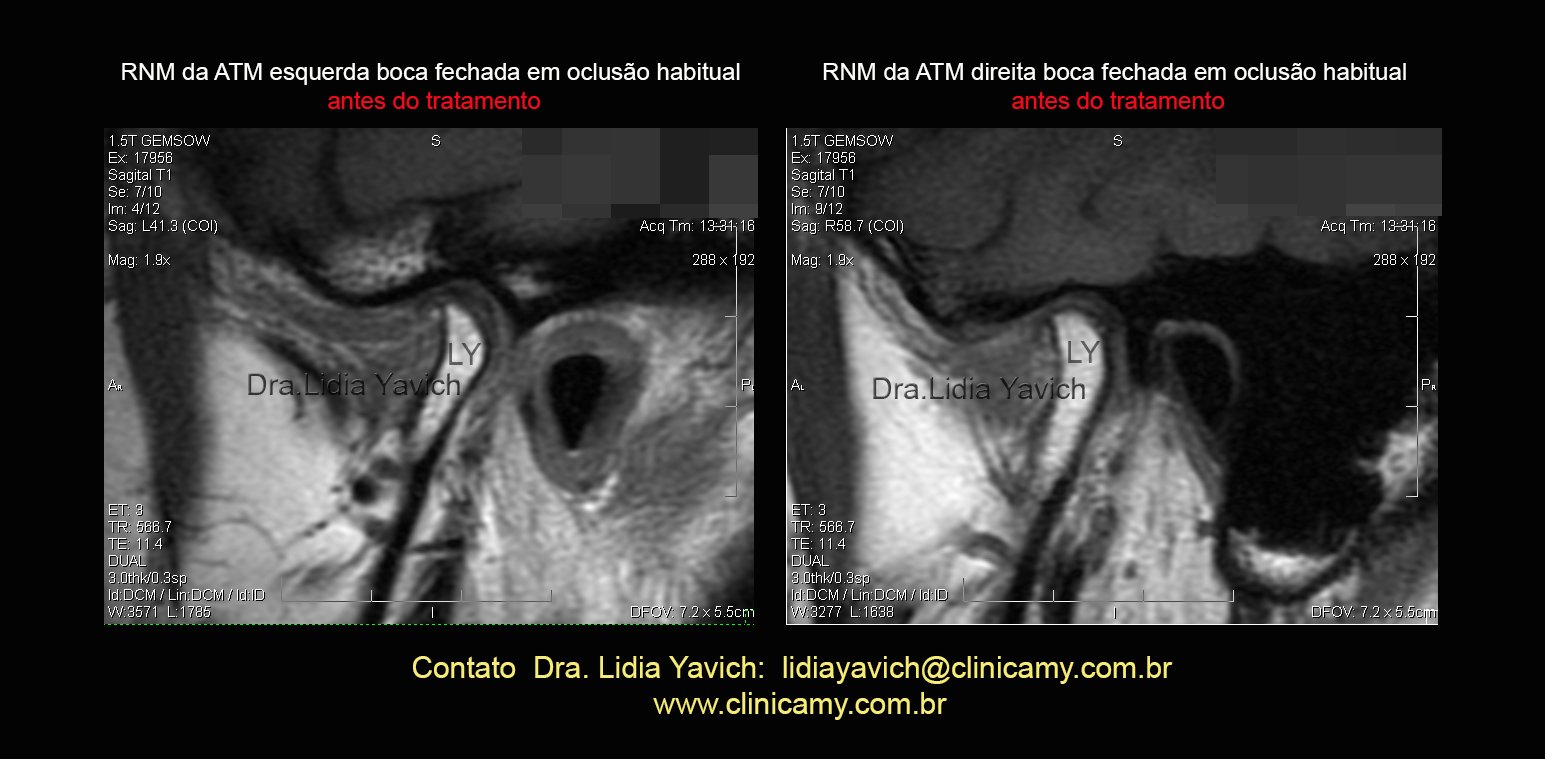

RNM em boca fechada das ATMs direita e esquerda: escolhi este corte para mostrar a assimetria importante entre o lado direito e esquerdo.

O lado esquerdo apresenta ainda uma LUXAÇÃO POSTERIOR do disco articular. O lado direito NÃO APRESENTA DISCO ARTICULAR é IMPORTANTE MARCAR ISTO, já que em vários posts eu mostro a importância de recapturar os discos quando possível, (NESTE CASO NÃO POSSO RECAPTURAR UMA ESTRUTURA QUE NÃO EXISTE).

Neste caso particular a solicitação da ressonância faz parte do protocolo para obter informações fundamentais na formulação do diagnóstico.

Os diferentes cortes e parâmetros não evidenciam edema ósseo nem outras informações que requeiram intervenções diferentes dentro do tratamento.